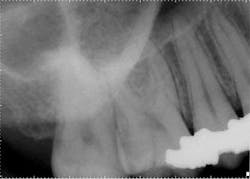

Exam: Teeth Nos. 2 through 5 responded normally to cold with no lingering and were asymptomatic to percussion, so the field of testing was expanded. Tooth No. 8 was nonresponsive to cold and heat. Both Nos. 7 and 8 were hypersensitive to percussion but had no restorative history, and the patient denied any history of trauma. There was no clinical evidence of an enamel defect associated with tooth No. 8. Radiographically, the apical and crestal bone was unremarkable around teeth Nos. 2 through 9. Teeth Nos. 3, 4, and 5 had significant restorative histories.Anterior preop

Treatment options: Root canal treatment No. 8, no treatment, or extraction. The patient was certain tooth No. 3 was the culprit, and No. 8 had no restorative or trauma history. As a result, waiting for symptoms to localize was a consideration. However, the patient experienced significant relief following administration of local anesthetic around tooth No. 8, and a root canal was completed.Posterior right